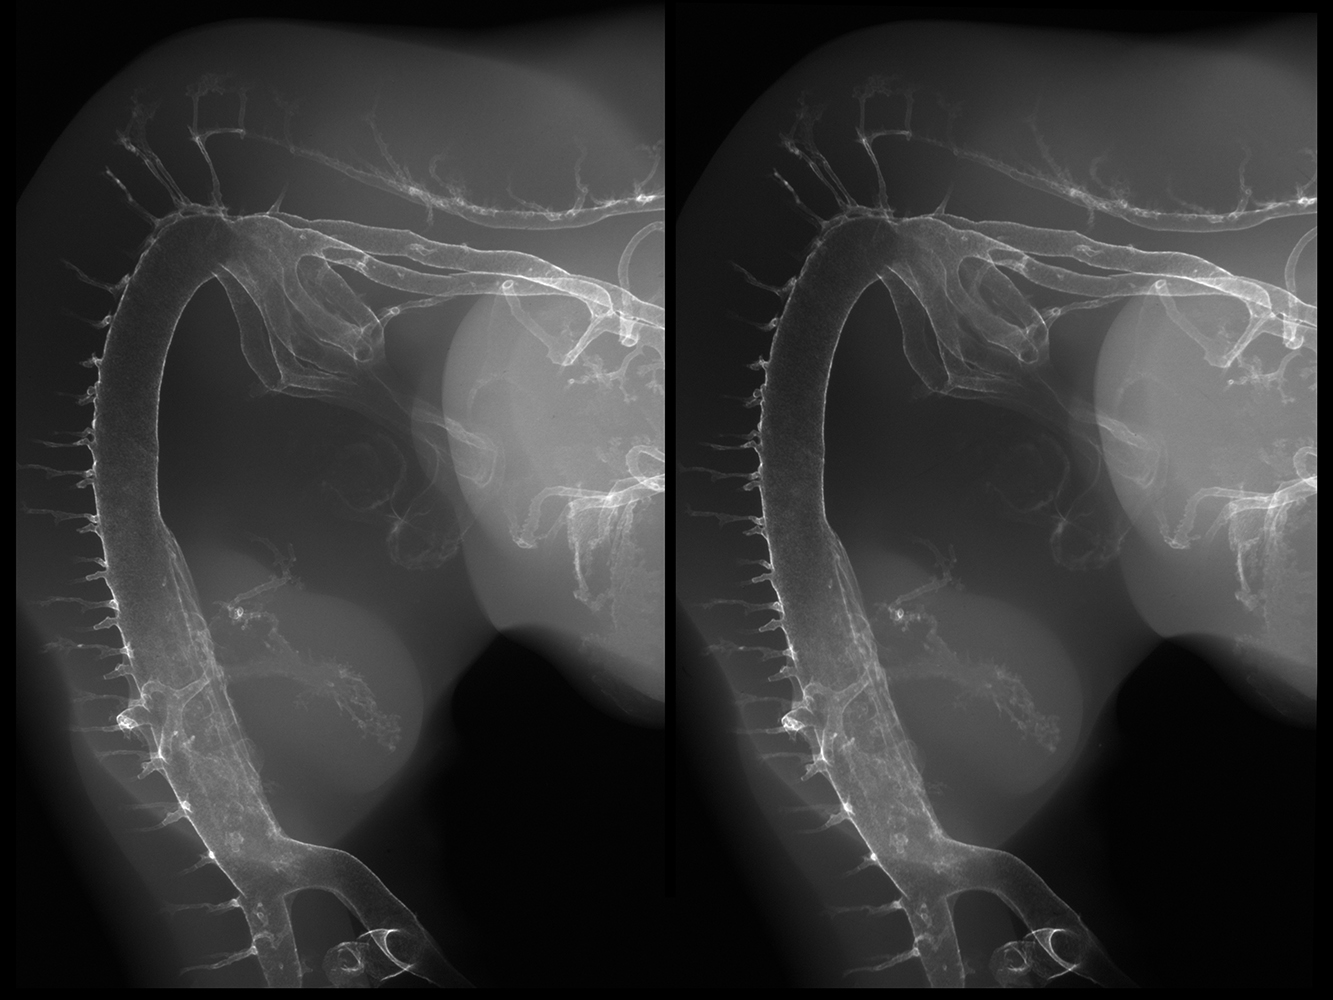

Viewing Cross-Eyed Stereo Images

The stereo-pair images on this website are positioned for “cross-eyed” viewing. This means the left image is intended for the right eye and the right image is intended for the left eye. The following process, with some practice, will allow you to direct the images to the appropriate eye without special glasses or other apparatus.

Sample Image For Practice

Chick Embryo X-rays Logo